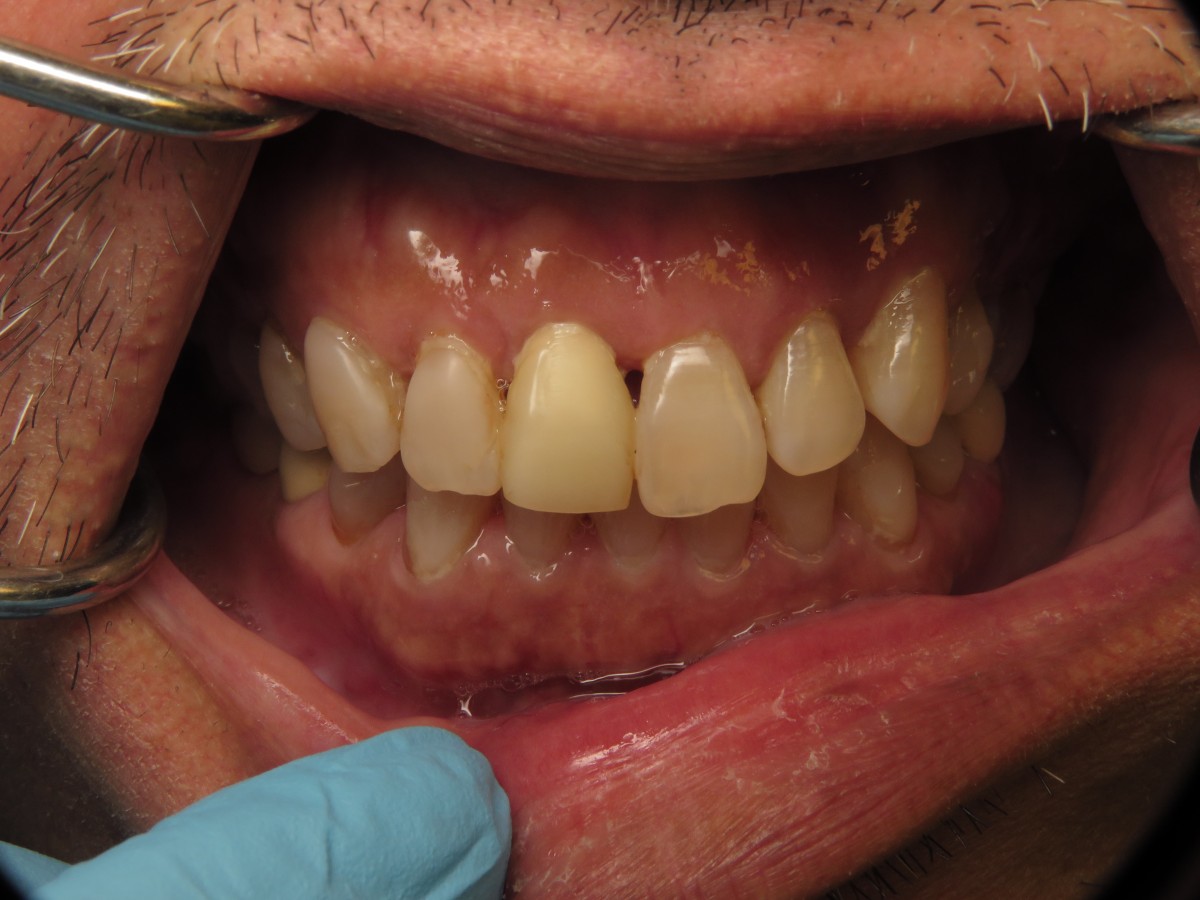

A 55-year-old male patient presented to our clinic seeking a solution for his failing anterior tooth (Figure 1). The tooth had been previously endodontically treated; currently it protruded coronally 1-2mm, had vertical bone loss in the mesial and grade II-III mobility (Figure 2).